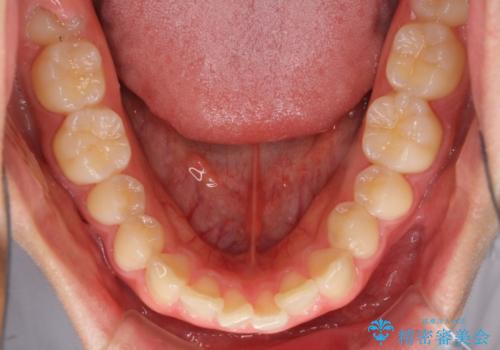

深い咬み合わせとデコボコ ワイヤー矯正で短期治療

- 前歯のデコボコを改善したいとのことで来院された患者様です。

インビザラインでの治療も可能でしたが、深い咬み合わせと奥歯の咬み合わせを改善するにあたり、ワイヤー矯正の方が治療期間を短縮できると判断し、ワイヤー矯正をお勧めしました。

結果として、1年かからずに奥歯の咬み合わせを改善することができました。